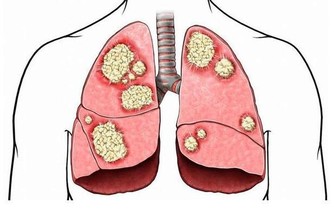

《黃帝內經》認為腎為“藏精之所,主骨生髓”,意即為生命的發動機,故古代醫家又稱腎為“先天之本”。腎藏精主生殖系統,如果生殖系統出現問題,比如說出現前列腺肥大,就說明腎的精氣不足了,要趕快補充精氣。老百姓常說“耳大有福”,背後的原理就是腎開竅於耳,腎氣充足則耳大飽滿、精力充沛,做事業自然拼勁十足、無往不利。曾國潘說“功名看氣宇,事業看精神”即是此意。經常耳鳴或者聽力下降的人,就是表明是腎氣不夠用了。什麼是腎主骨呢?中醫認為,人的骨骼強健與否,由腎精氣盈虧所決定。骨質疏鬆的人要補養腎的精氣,腎的精氣足了,骨骼就強健有力了。

人散步的時候會有很多生理反應,其中一個反應就是滿口生津。這代表你的腎氣、腎精得到補充了,因為在五行學說裡面唾液歸屬於腎水。所以腎陰虛的人口裡會經常乾,缺少唾液,這就是腎精不足了。那麼腎精氣不足會出現哪些症狀呢?常見的有腰膝酸軟、手腳冷、體虛乏力、耳鳴、脫髮、牙齒鬆動、骨質疏鬆、夜尿多、前列腺肥大、性功能減退、不孕不育、腎虧、更年期綜合症。